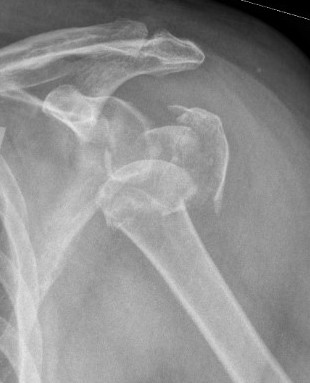

Severe comminuted proximal humerus fractures

100% displaced / off ended

Fracture - dislocations

Unreconstructable fracture - 4 part, comminuted, head spltting fracture